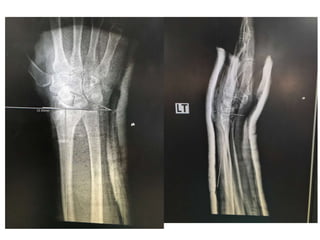

Film X ray

• Left wrist AP ,lateral

Diagnosis

• Closed fracture at left distal end radius

Film after on slab

Film X ray •Left wrist AP ,lateral